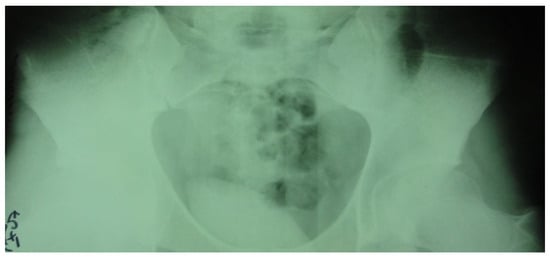

In the second case, the patient, a left back, experienced pain in the inguinal region and left thigh while running during a national team training session. This 23-year-old national team member has six years of experience as a first-league professional in Romania, standing 202 cm tall and weighing 105 kg. Pelvic radiography was incorrectly performed (incorrectly) and the patient was diagnosed with left thigh muscle damage. (Figure 4).

Figure 4.

Incorrect pelvic X-ray.